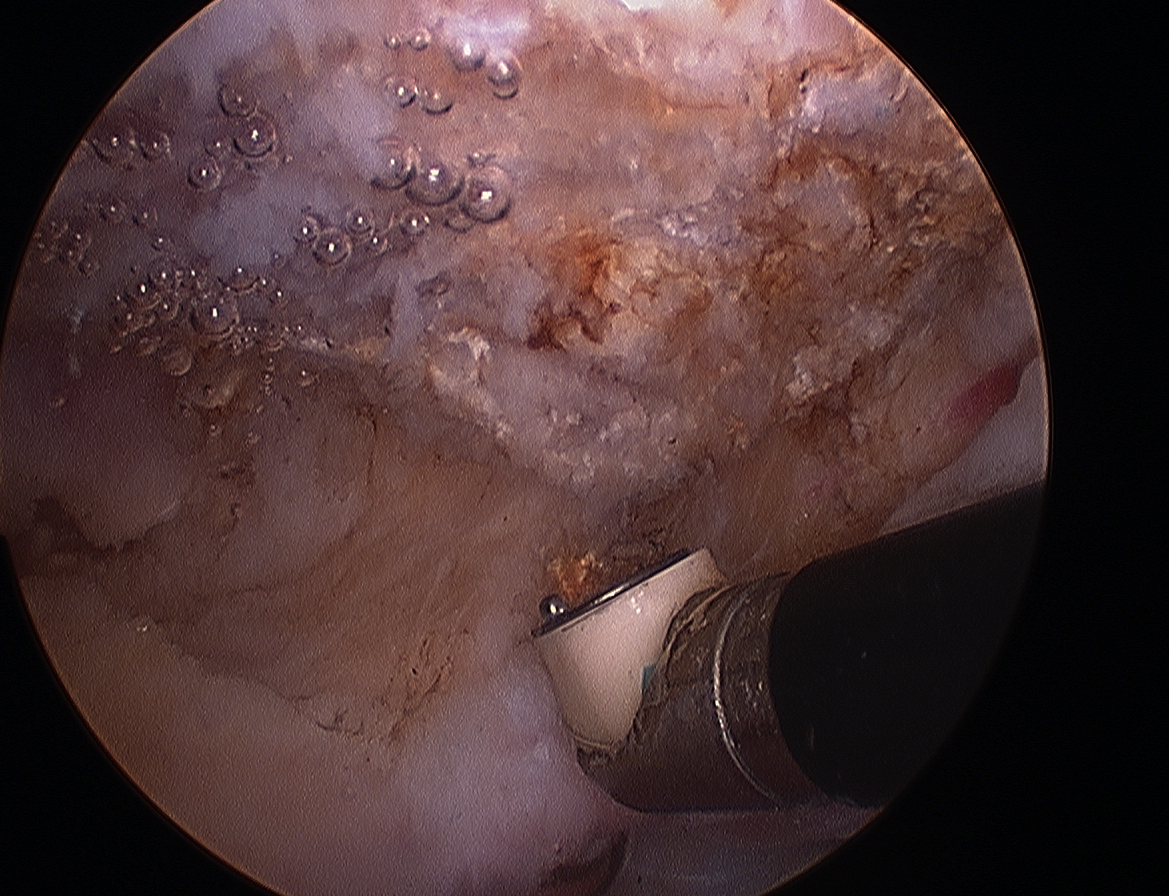

Arthroscopic acromioplasty

Technique

Beach chair / lateral

- posterior viewing portal subacromial space

- lateral working portal

- bursectomy with shaver

- electrocautery to release / resect CA ligament

- use burr to perform anterior acromioplasty

CA ligament above shaver and cuff

Large acromial spurs

Spur resection